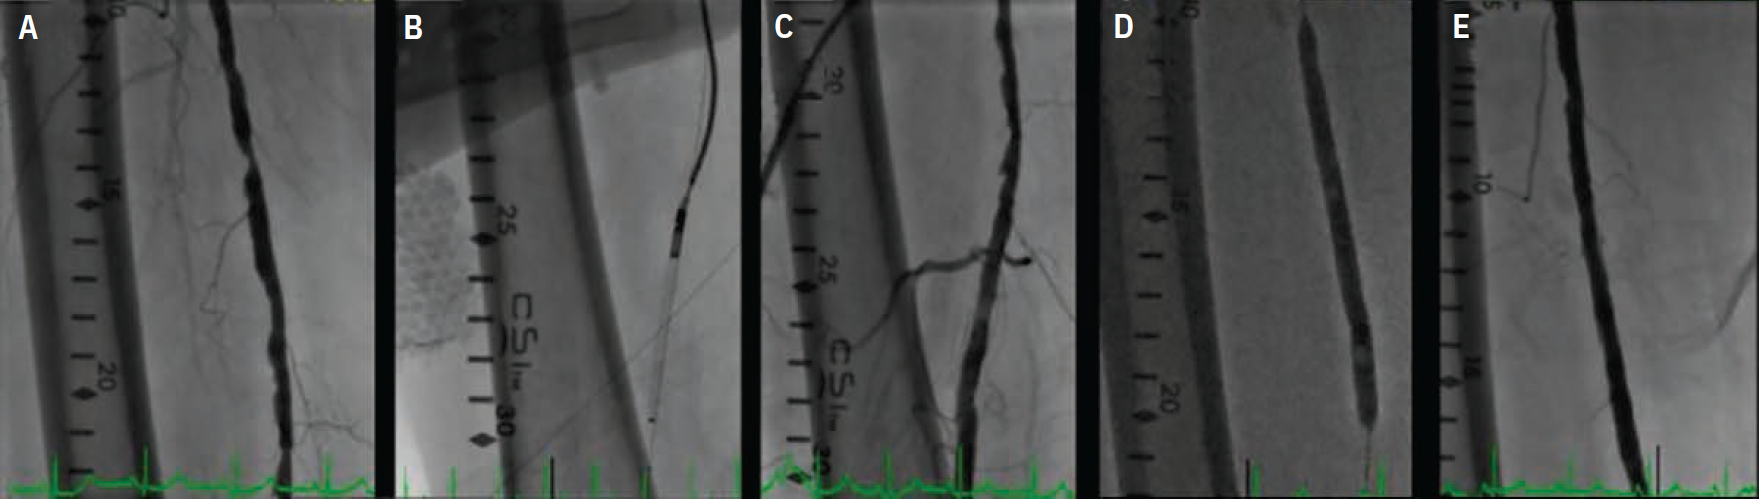

A 58-year-old female with a history of hypertension, hyperlipidemia, and tobacco use presented with Rutherford class III right lower-extremity claudication and an abnormal ankle-brachial index (ABI) of 0.5 despite maximal medical therapy and supervised graded exercise program. She was referred for direct peripheral angiography and possible intervention. Her peripheral angiography showed a long chronic total occlusion (CTO) of the right superficial femoral artery (SFA) extending from its ostium to the mid-distal segment, reconstituting in the adductor canal via collaterals (Figure 1A-C). A 6 French (Fr) crossover sheath was placed in the left common femoral artery and an .035-inch angled Glidewire (Terumo Interventional Systems) was advanced into the right SFA ostium. After dissection with subintimal tracking and reentry into the distal true lumen, the Glidewire was advanced to the right popliteal artery. It was then exchanged for an .014-inch guidewire and frequency domain (FD) OCT (C7-XR; Abbott) of the SFA was performed by injecting dextran to clear the blood. OCT imaging demonstrated long dissection planes with false and true lumens (Figure 2A-C). After confirming that the guidewire was in the true lumen, balloon angioplasty was performed using a 5.0 mm x 200 mm balloon, and the lesion was stented with a 5.0 mm x 220 mm Supera stent (Abbott) and post dilated with a 6.0 mm x 200 mm balloon (Figures 1D-F). Repeat OCT after stent deployment showed optimal stent expansion and wall apposition (Figures 2D-F). The patient was placed on dual antiplatelet therapy with significant clinical improvement and normalization of her ABI at 30-day follow-up.